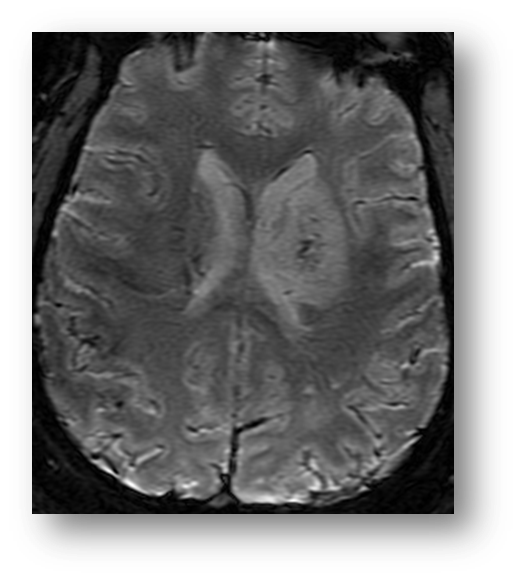

Refer to caption

Figure 1: T2 axial fast spin echo image showing acute ischemia in the PCA distribution. There is relative hyperintensity in the left occipital region of infarction. Note the prominent hyperintensity of the vitreous and cerebrospinal fluid, both consistent with the hyperintensity of water on T2-weighted imaging.

where Mxy(0)subscript𝑀𝑥𝑦0M_{xy}(0) is the transverse magnetization instantaneously after pulse excitation. Following the B1subscript𝐵1B_{1} induction of in-phase precession, the proton spins again begin to dephase according to T2subscript𝑇2T_{2} time constant. Of note, the relaxation of transverse magnetization is faster than the recovery of longitudinal magnetization. In other terms, T2<T1subscript𝑇2subscript𝑇1T_{2}<T_{1}. Figure (1) shows a T2 fast spin echo image of acute ischemic stroke in the posterior circulation.